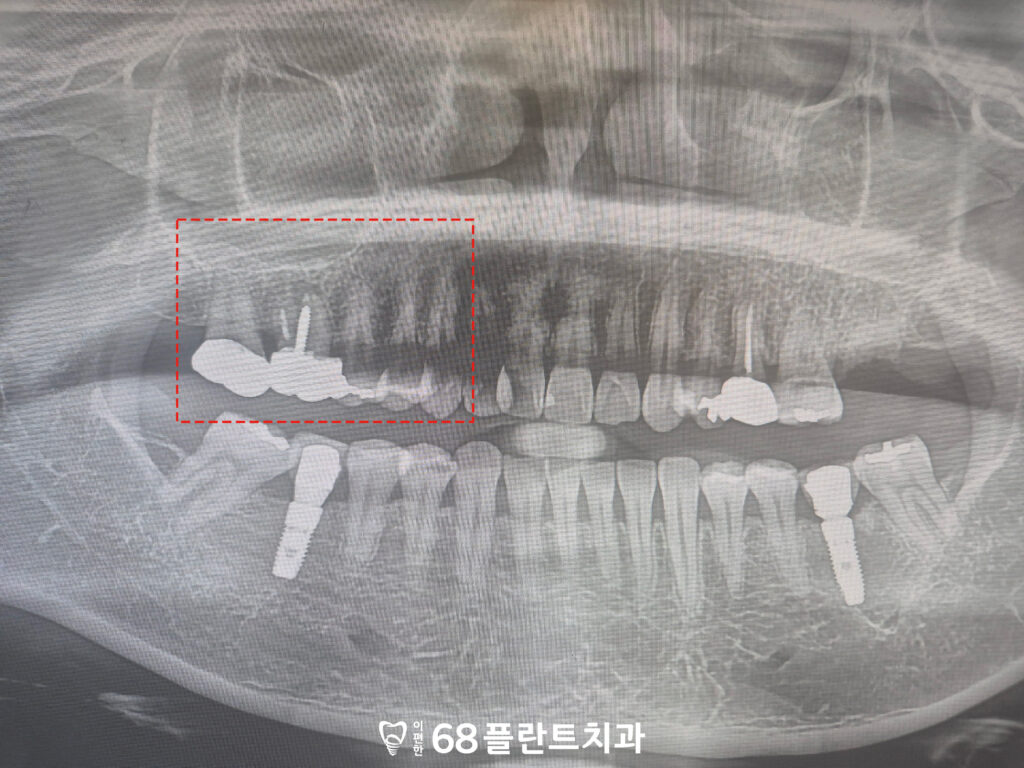

◆ 전 > 후 ◆

철산역치과 철산역치과

치료 마무리 후 사진입니다.

환자분께서는 치아에 생긴 금으로 인해

식사를 편하게 하지 못해

많이 힘들어하셨으나,

치료 후에는 저작 시 느껴지던 불편감이 줄어들어

식사를 한결 편안하게 하실 수 있게 되었고

결과에도 만족해 주셨습니다.

또한 식립 후 약 20년 동안

꾸준히 내원하시며 정기적인 검진과

관리를 이어오신 덕분에

임플란트 역시 큰 문제 없이

안정적인 상태를 유지할 수 있었습니다.